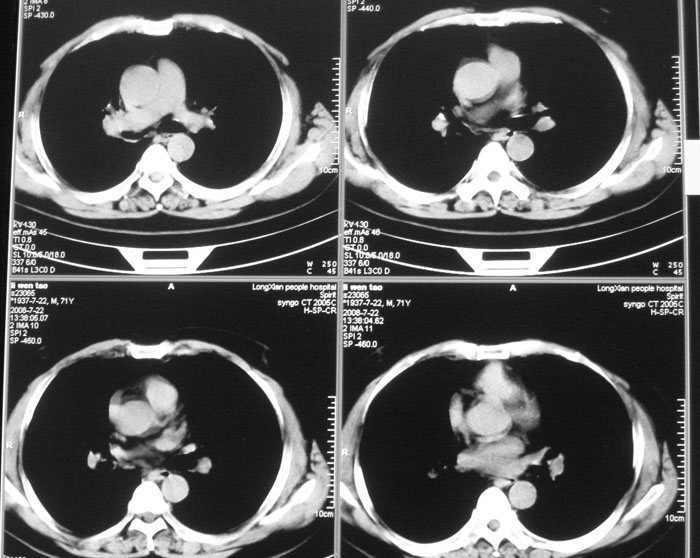

以下是引用wwwwtyy在2008-7-27 17:46:00的发言:[br]中心型肺癌不除外

以下是引用子十在2008-7-27 17:49:00的发言:[br]考虑中心性肺癌

以下是引用晓杰在2008-7-27 19:20:00的发言:[br]支持楼主意见;中心型肺癌不除外。

以下是引用zhangjixiang在2008-8-6 20:02:00的发言:[br]右主支气管明显变窄伴右上叶尖段不张,结合年龄,考虑右侧中央型肺癌可能性大,纤支镜检可确诊.